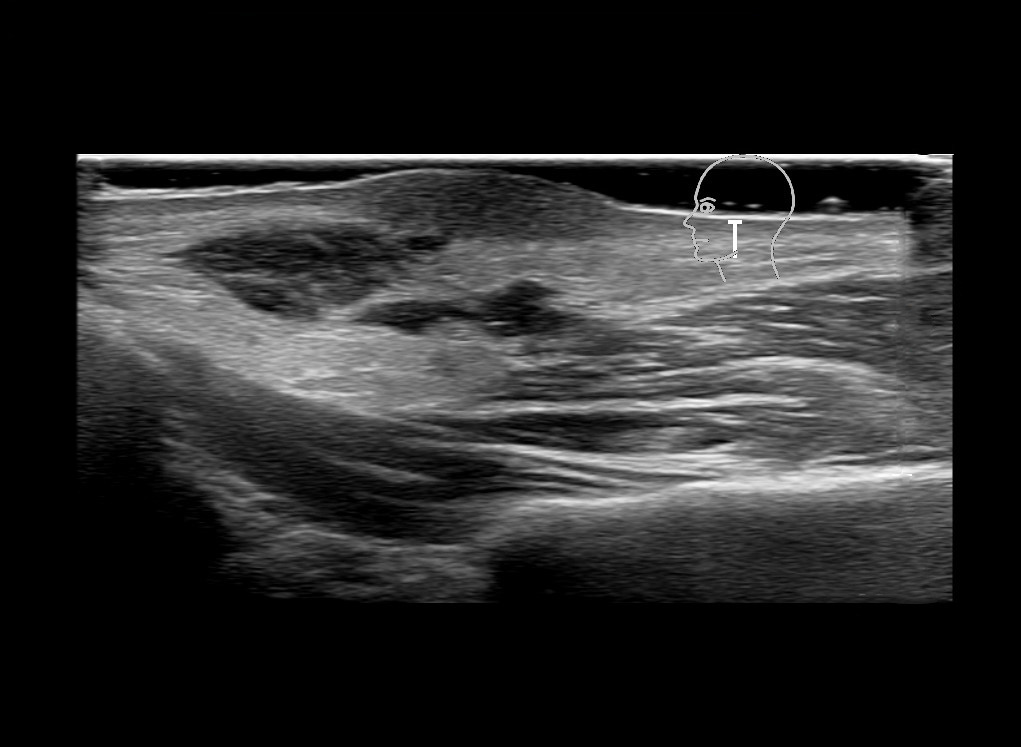

Study the first image to recognize the different layers. If you are sure about the layers, swipe to the second image to view the answer (if applicable).

Hover over an image to view the secondary image or click on the image title for more information.